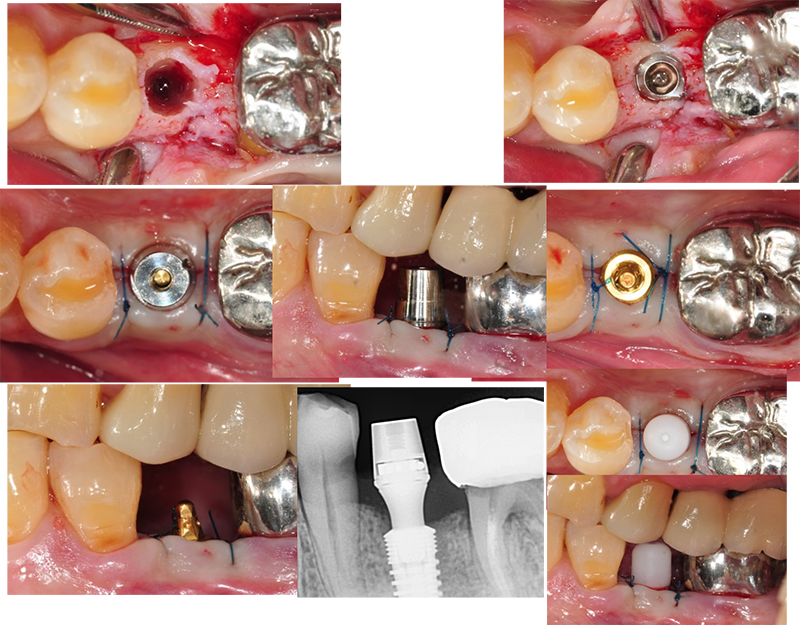

ÀÓÇöõÆ®´Â cortical bone ¼Õ»óÀ» ÃÖ¼ÒÈ Çϱ⠶§¹®¿¡ Ãʱâ°íÁ¤ÀÌ ¸Å¿ì ÁÁ´Ù.

Áï½ÃºÎÇϰ¡ °¡´ÉÇÏ´Ù´Â ¸»ÀÌ´Ù.

¹Ù·Î EzcÀÇ convertible abutment(Ezc ab)¸¦ ÀåÂøÇÒ ¼ö ÀÖ´Ù. ¸Å¿ì ¾ÈÁ¤ÀûÀÎ º¸Ã¶ µðÀÚÀÎÀÌ µÉ ¼ö ÀÖ´Ù.

¼ö¼úÇÏ°í ¹Ù·Î convertible abutmentÀÎ Ezc ab¸¦

ÀåÂøÇϰí ÀλóÀ» 䵿Çß´Ù. Àӽú¸Ã¶¹°À» ¸¸µé±â À§Çؼ´Ù.

Ezc convertible

abutment¸¦ À§Ä¡½Ãų ¶§ ¼ö¼ú Á÷ÈÄÀ̹ǷΠÀÕ¸öº¸´Ù 1.0~1.5mm ÇϹ濡 À§Ä¡½Ã۸é ÁÁ°Ú´Ù.

Abutment level

impression(fixture level impressionÀÌ ¾Æ´Ï°í) Áï Áö´ëÁÖ ·¹º§ ÀλóÀÌ´Ù. ¹°·Ð º¸Ã¶µµ Áö´ëÁÖ ·¹º§ÀÇ º¸Ã¶ µðÀÚÀÎÀÌ µÉ

°ÍÀÌ´Ù.